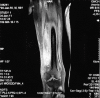

Diabetic myonecrosis is an underreported complication of long-standing, poorly controlled diabetes mellitus which is usually self-limiting and responds well to conservative management. Patients frequently have microvascular complications, and although short-term prognosis is good, the long-term prognosis is poor. We report four cases of diabetic myonecrosis admitted in a tertiary care hospital.